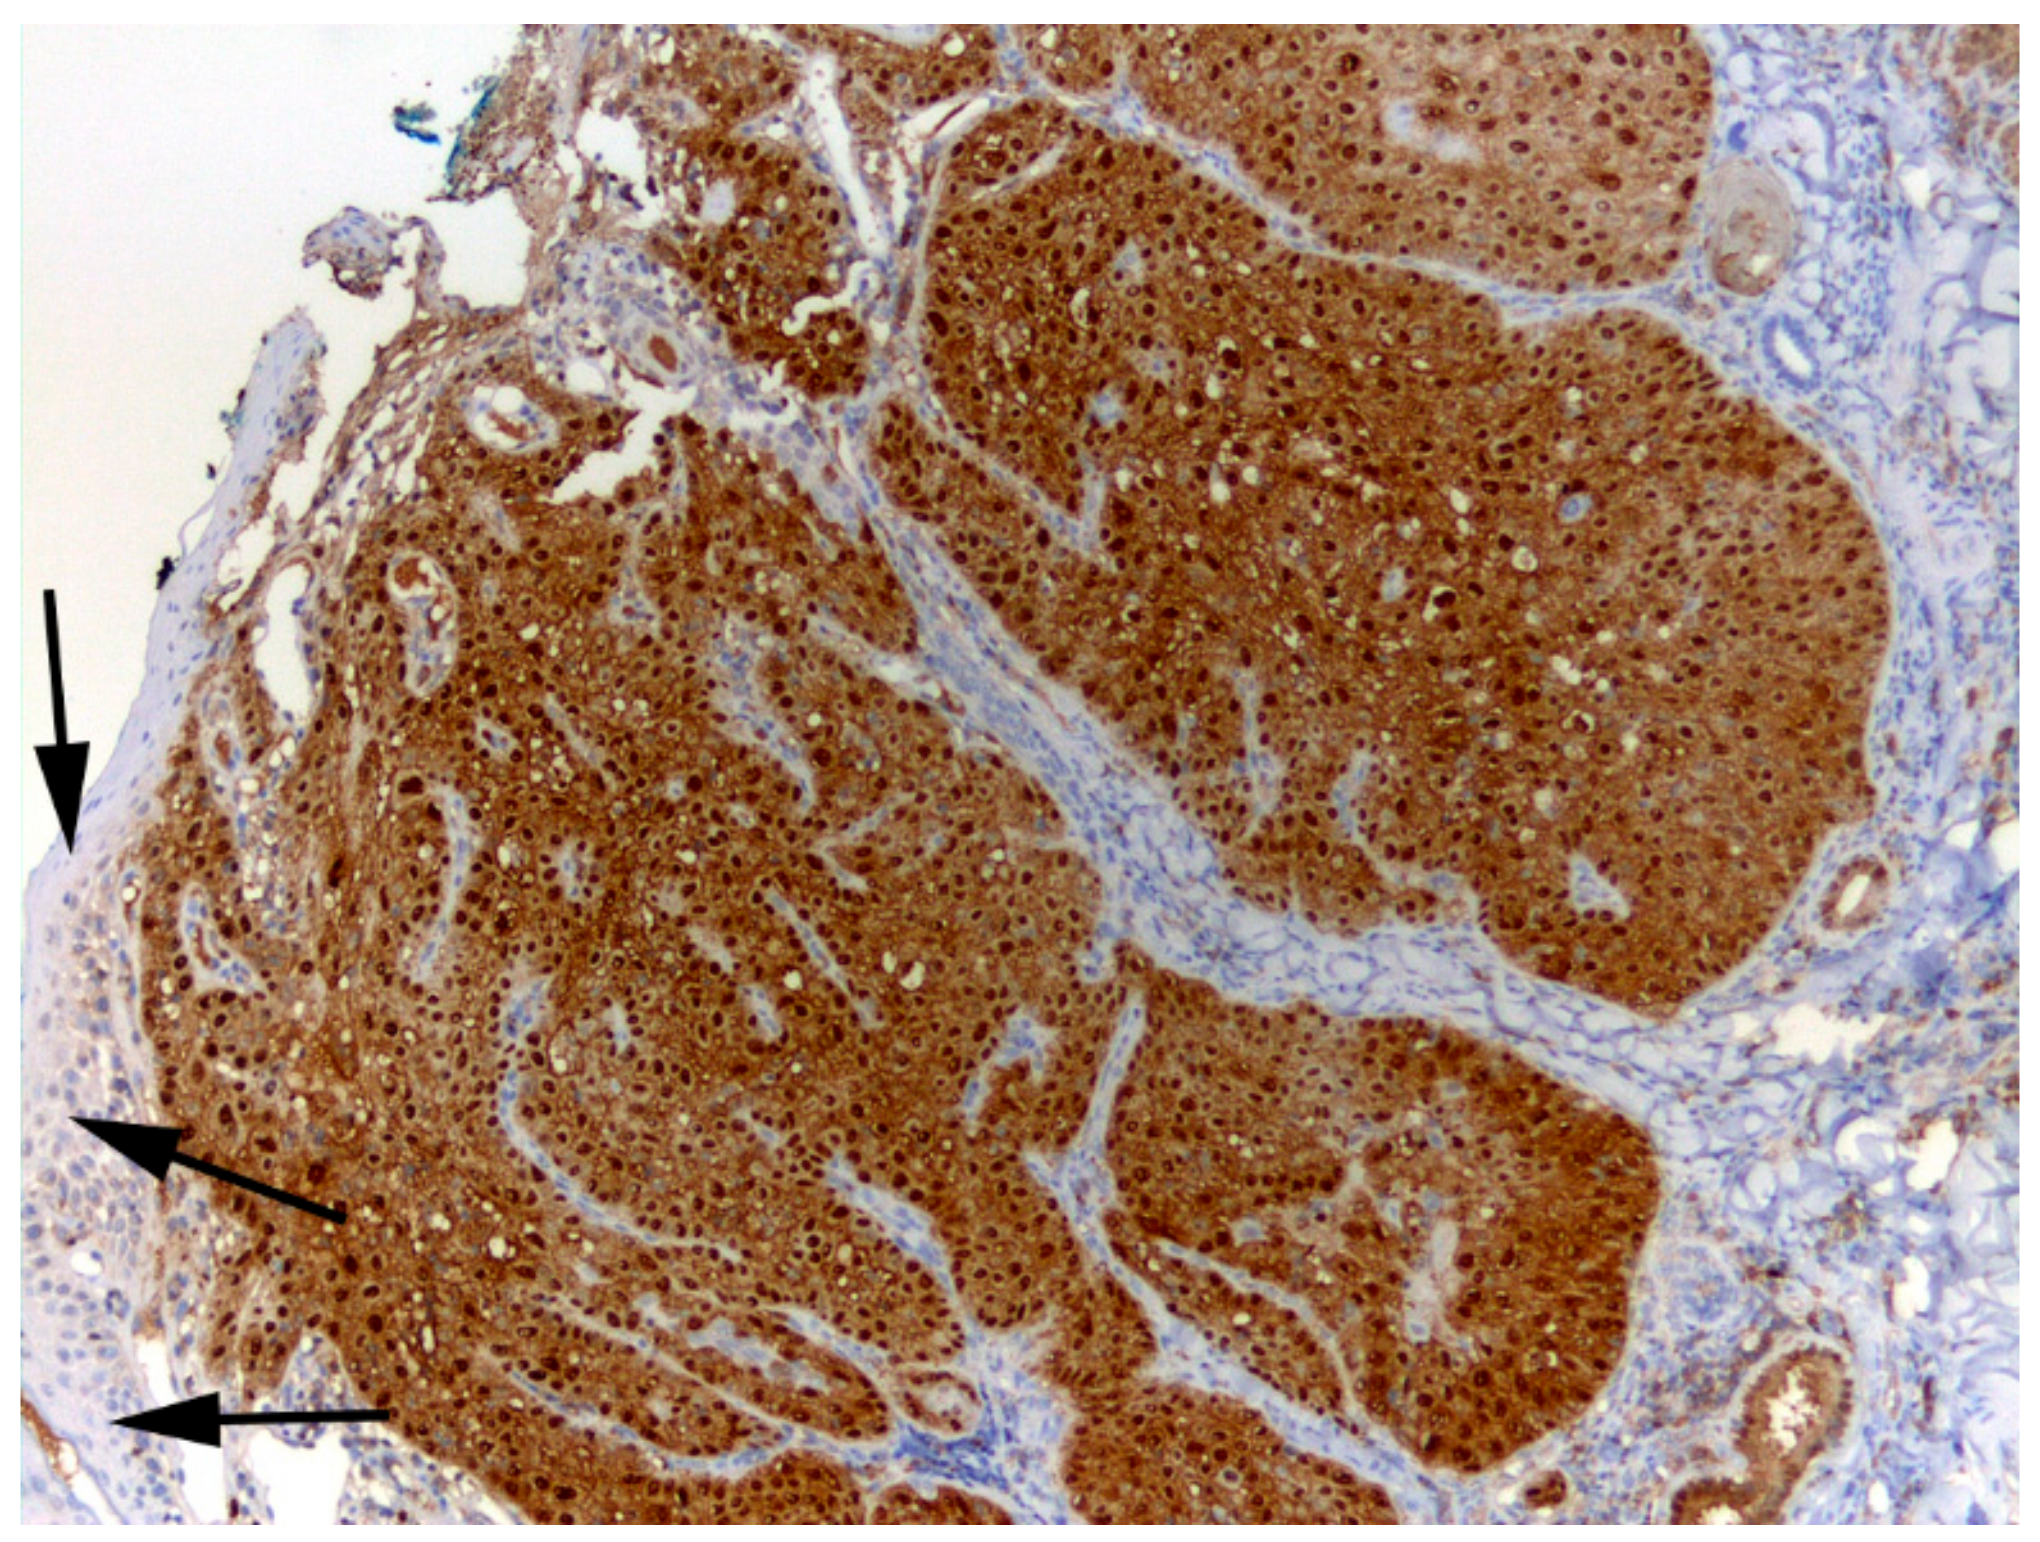

2.4.3. p16 Immunostaining

3.3. Association of FcaPV6 with Squamous Cell Carcinoma